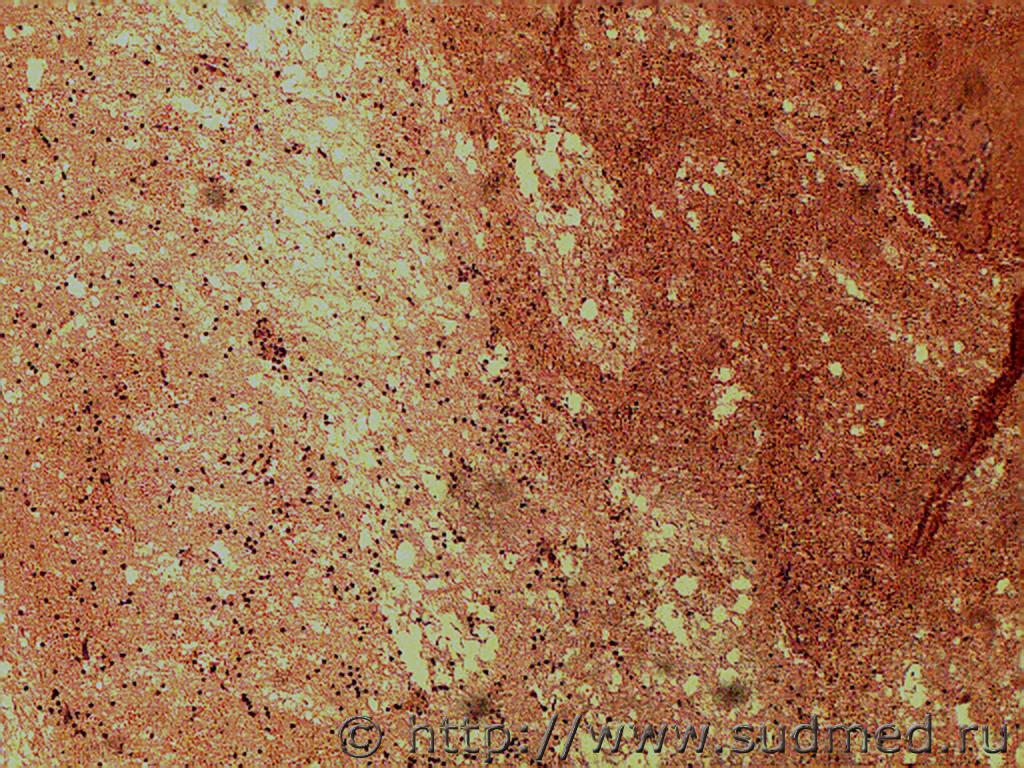

Уважаемые коллеги, пожалуйста, помогите разобраться со скандальным случаем! Из обстоятельств: выпивший мужчина въехал в металлический забор соседей, хозяин забора вытащил мужика из машины и несколько раз ударил по лицу, после чего тот потерял сознание (так в сознание больше и не пришёл). В больнице в приёмнике выставлена кома 2, через 3 дня- кома 3 и смерть. АД 215/141, пульс 160 в мин; об-но: разгибательная реакция на болевые раздражители (хуже справа), фотореакция отсутствует, корнеальные рефлексы вялые, , окулоцефалические рефлексы угнетены. Лицевая мускулатура симметричная. Мышечный тонус- без субъективной разницы сторон, снижены, сухожильные рефлексы с рук торпидные; симптом Бабинского положительный с обеих сторон. Т.к. в больнице сломан аппарат МРТ, выставлен конкурирующий диагноз:1. Ушиб ГМ мезенцефалобульбарная и диэнцефальная форма. 2.Ишемический инсульт в вертебро- базиллярном бассеине. Соп: ИБС, ГБ. В течение 3-х суток состояние ухудшалось, переведён на ИВЛ, смерть. На вскрытии пеломов костей черепа нет, в желудочках 150 мл крови со свёртками. Размягчение вещества мозга в области всех стенок боковых желудочков, мозолистого тела, стволового отдела на глубину от 0,5 до 1,5 см. в зоне размягчения в-во мозга серовато- красноватого цвета с мелкоочаговыми кровоизлияниями; в области дна 3-го желудочка под ММО распространяются кровоизлияния, располагающиеся на основании височных и лобных долей, а также кровоизлияние распространяется под ММО ствола. В веществе ствола мелкоочаговые полосчатые кровоизлияния. Выраженные признаки ГБ, атеросклероз сосудов мозга. Источник кровоизлияния в желудочки не найден. Выкладываю микрофотографии, заранее извиняюсь за качество, т.к. камера плохая. Кратко скажу, что в препаратах ствола САК; ишемия, нейроцитолиз нейронов. Ткань мозга сетчатая, выраженный периваскулярный, перицеллюлярный, периаксональный отек, отёк белого вещества. В препаратах основания правой лобной доли САК, очаговые геморрагии в подкорковых отдела; на одном из препаратов попалась вена с разрывом, стенка её с дегенеративными изменениями, неравномерно истончена со скоплением гомогенных эозинофильных масс, очаговой круглоклеточной инфильтрацией (не знаю как назвать такую патологию, на аневризму, мальформацию не похоже). В подкорковых узлах левого и правого полушарий ткань мозга сетчатая, выраженный периваскулярный, перицеллюлярный, периаксональный отек, отёк белого вещества; местами очень похоже на аксональные шары, но боюсь ошибиться с ДАП, т.к никаких нейроокрасок у нас нет. Родственники трубят тревогу, а я никак не могу закончить экспертизу, мучаюсь, боюсь пропустить травму, не дай Бог, ДАП, хотя склоняюсь к заболеванию, хотя ишемический инфаркт в данном случае тоже сомнителен. По препаратам выраженный атеросклероз сосудов, базиллярная артерия сужена на 40%. Смущает источник кровотечения в желудочки, его на вскрытии не нашли.

Эскизы прикрепленных изображений